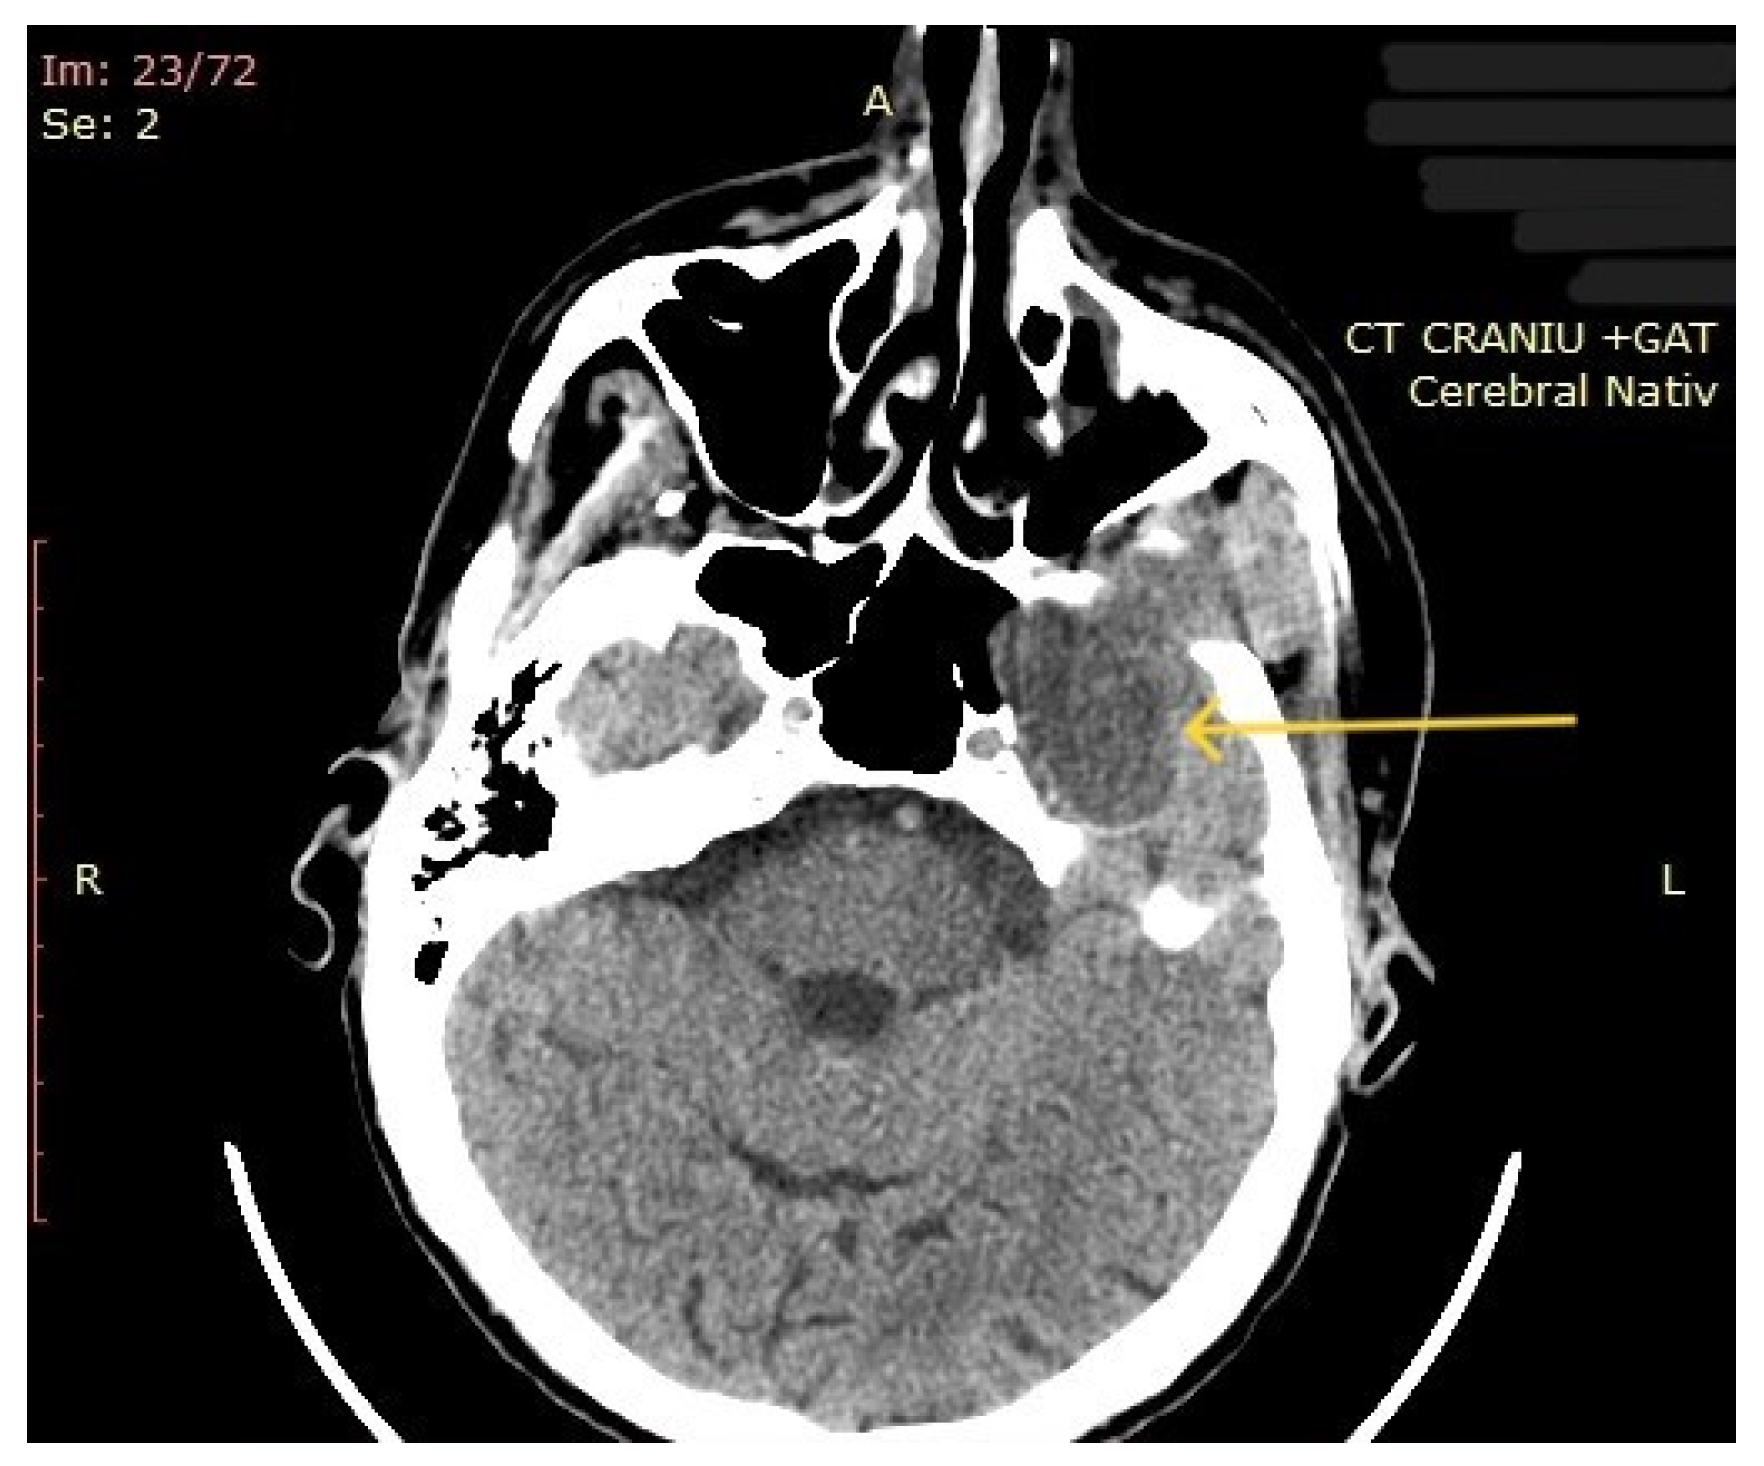

| 10 | Left parapharyngeal region with maxillary and intracranial extension | Discomfort in breathing, chewing, swallowing, phonation, sleeping, regional pain, fatigue | 5 years | 10 cm | Benign tumor of soft tissue |